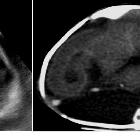

Antenatal ultrasound

Thus identification of a dividing membrane or two placentas excludes the diagnosis. Definitive sonographic features will depend on the type of fusion.

General features include:

- lack of a separating inter-twin membrane

- non-separable skin contours with an inability to separate the fetal bodies

- detection of other anomalies in a twin gestation

- solitary umbilical cord with more than 3 vessels present

- both fetal heads persistently at the same level

- backward flexion of the cervical spine (due to the fact that most conjoined twins are fused ventrally and face each other

- bibreech or less commonly, bicephalic presentation

- constant relative fetal positions